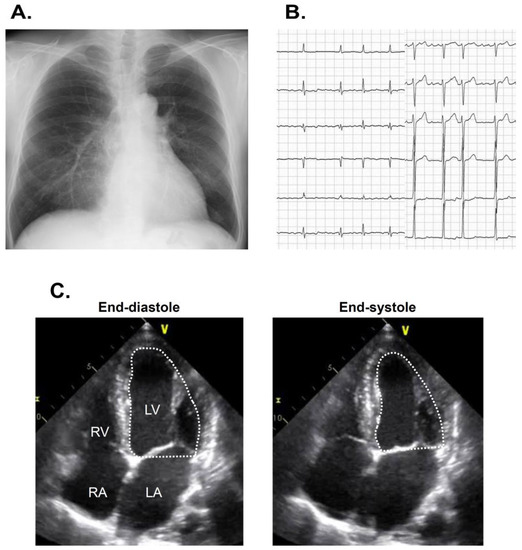

The estimated glomerular filtration ratio was 57 mL/min/1.73 m2, plasma B-type natriuretic peptide was 72 pg/mL, and hemoglobin A1c was 6.7%. Chest X-ray showed 46% of cardiothoracic ratio without obvious pulmonary congestion (Figure 1A). An electrocardiogram showed 91 bpm with atrial fibrillation (Figure 1B). Transthoracic echocardiography showed 50 mm of left ventricular end-diastolic diameter, 44 mm of left atrial diameter, and 40% of left ventricular ejection fraction calculated using a modified Simpson’s method (Figure 1C).

Figure 1.

Chest X-ray showing 47% of cardiothoracic ratio (A), electrocardiogram showing atrial fibrillation (B), and transthoracic echocardiography showing reduced left ventricular ejection fraction on admission (C) on admission. LA, left atrium: LV, left ventricle; Ao, ascending aorta; RA, right atrium; RV, right ventricle.